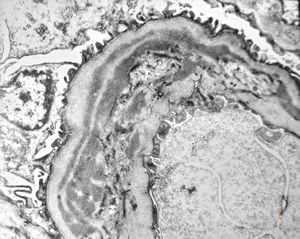

M,13y. | thin basement membrane syndrome